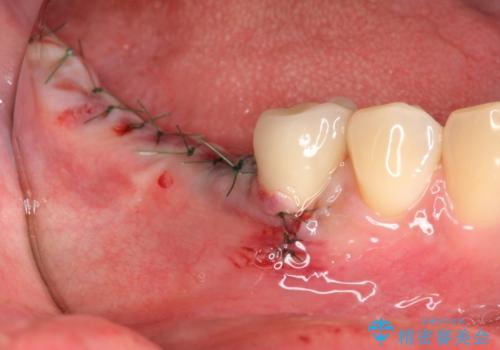

インプラントの埋入には十分な骨量が必要ですが、虫食い状に骨が足りなかった為インプラントの埋入と同時に骨の増成を行いました。

インプラントを埋入する手術と同時に骨の増成を行う場合と、埋入前に骨の造成だけを行う場合があります。